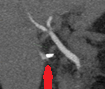

Yellow arrow — Contrast collection in the gallbladder fossa. Red arrow — Injured Luschka duct (Courtesy Dr. V. Penopoulos)